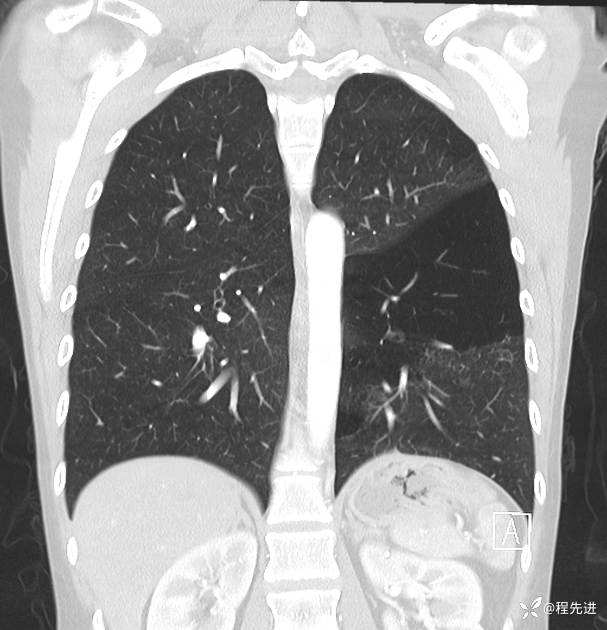

患者性别:女

患者年龄:25岁

简要病史:下胸部疼痛3天

CT增强:

img